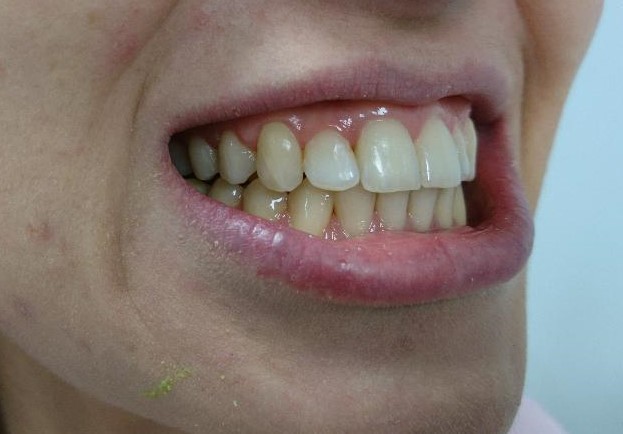

Pacient, 26 ani. Caz nonextracționist, Expander Maxilar + aparate ortodontice fixe bimaxilare.